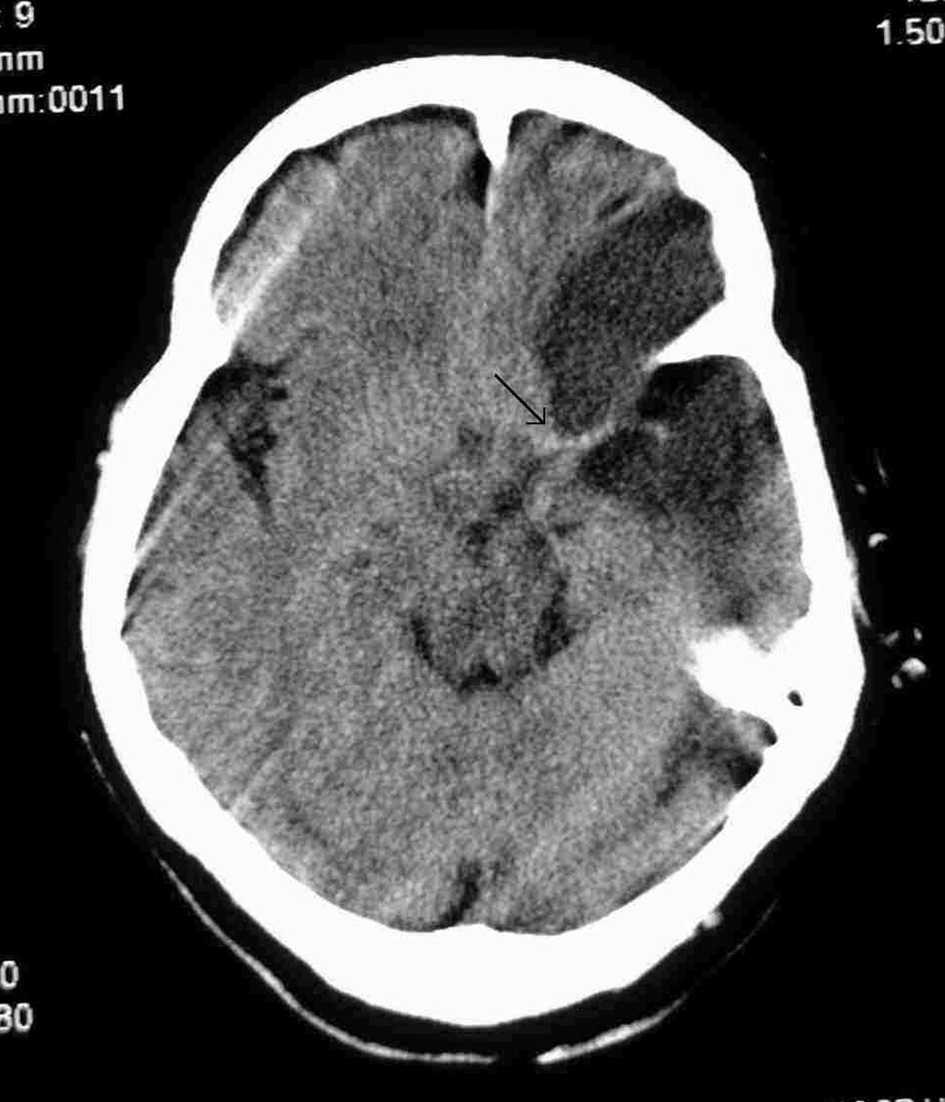

Paciente de 73 años con antecedentes de hipertensión arterial (HTA), diabetes no insulino-dependiente, hipotiroidismo, hipercolesterolemia y bronquitis crónica. Fue trasladada a nuestro hospital por el servicio de emergencias extrahospitalaria por un cuadro brusco de insuficiencia respiratoria y disminución del nivel de conciencia con hemiparesia derecha. A su ingreso en el hospital está intubada con Glasgow Coma Score (GCS) 6, presión arterial (PA): 240/100 mmHg, anisocoria con midriasis izquierda, hemiplejía derecha y Babinsky derecho. Se realiza tomografía axial computarizada (TAC) cerebral (fig. 1) que aprecia hiperdensidad de la arteria cerebral media derecha como signo precoz de lesión isquémica que todavía no se visualiza. Al ingreso en nuestra unidad se la mantiene sedada, en ventilación mecánica, controlando la PA y con tratamiento antiagregante. A las 48 horas se repite la TAC (fig. 2), observándose trombosis de la arteria cerebral media izquierda e hipodensidad frontotemporoparietal izquierda. Se mantiene consciente, afásica y hemipléjica pudiendo ser extubada y trasladada a planta. Posteriormente fallece por las secuelas de su enfermedad. El diagnóstico fue accidente cerebrovascular agudo (ACVA) isquémico y trombosis de la arteria cerebral media izquierda.